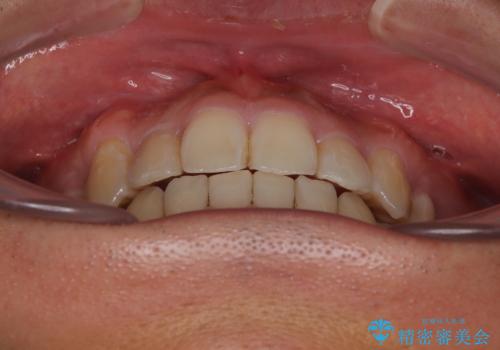

八重歯はきれいに整い、前歯もバランスよく収まり、横顔のラインも自然に改善されました。

治療後、患者様は「思い切り笑えるようになった」と大変喜んでくださいました。